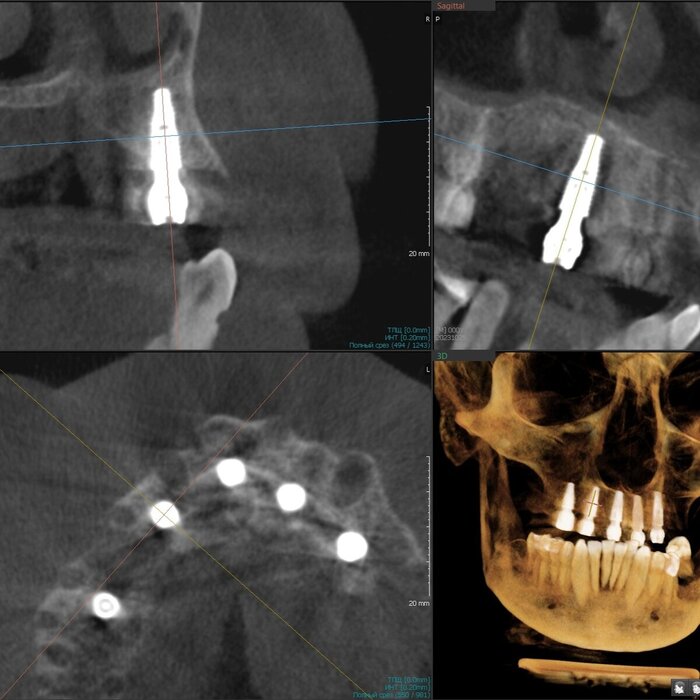

Имплантаты установлены - 5 штук. Были мысли насчёт 6-ти, даже шаблоны сделаны с этим расчётом. Но - обильное кровотечение и малек количество кости не оставили шансов. Мы не рискуем. Делаем на 5-ти, 6-ой имплантат будет установлен позже, через несколько месяцев.

Делаем промежуточное фото. Это нужно, что бы хирург видел, есть ли необходимость имплантаты "докрутить". Да, есть - 2 штуки можно углубить на 2 мм каждый.

Давайте посмотрим на каждый имплантат - на все 5 штук.

1. Область зуба 2.4.

2. Область зуба 2.2

3. Область зуба 1.2

4. Область зуба 1.4

5. Область зуба 1.7